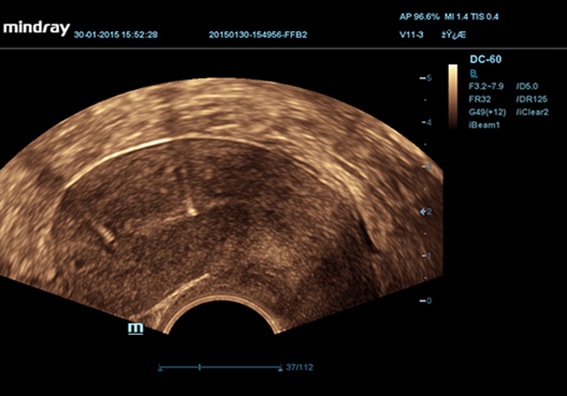

• Внутриполостной датчик Mindray V11-3

• Ректально-вагинальный датчик Mindray V11-3B